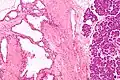

Micrograph showing a pancreatic serous cystadenoma. H&E stain. | |